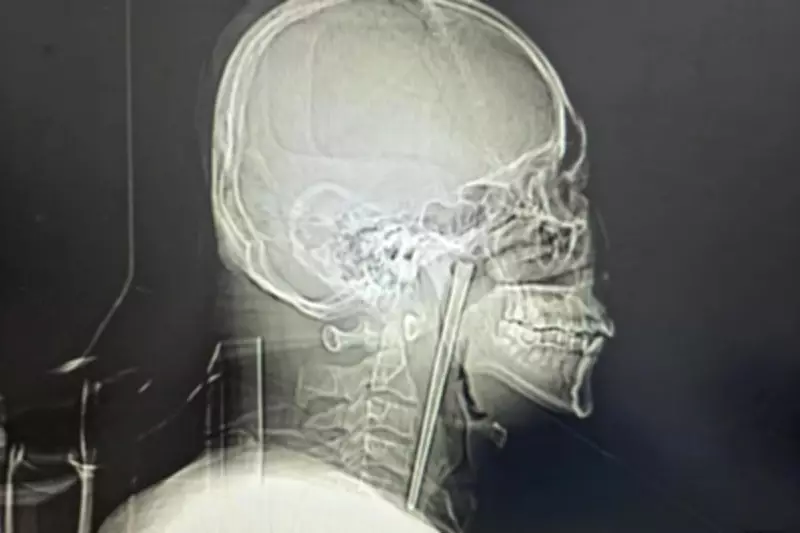

Man Endures Eight Years with Metal Chopstick Lodged in Throat Before Surgery

A startling medical case from China reveals that a man lived for eight years with a metal chopstick stuck in his throat after swallowing it during a meal. The patient, identified only as Mr. Wang, finally underwent surgery in March 2026 to remove the five-inch utensil, which had caused increasing discomfort over time.

According to a hospital case study published in March, the 46-year-old man, described as an alcoholic, accidentally gulped down the chopstick in 2018 while eating dinner. He sought a medical check-up shortly after the incident but refused to have it removed at that time. Wang was reportedly unwilling to undergo a procedure that would involve cutting open his neck, leading him to tolerate the foreign object for years.

Several weeks before the surgery, Wang experienced escalating difficulty swallowing, prompting him to visit Dalian Municipal Central Hospital in Liaoning Province for evaluation. Doctors were astonished to learn that the chopstick had been trapped in his throat for nearly a decade. Dr. Huang Weipeng, one of the surgeons involved, recounted, "He told us a chopstick was trapped in his throat. I thought it happened just now, but he said this was eight years ago."

Minimally Invasive Procedure and Recovery

Surgeons performed a minimally invasive operation to extract the chopstick through Wang's mouth, avoiding the need to slice open his neck. The hospital report noted that his vocal cords and nearby mucous membrane were fortunately not injured and functioned normally post-surgery. Wang was discharged from the hospital days later and is expected to make a full recovery, highlighting the successful outcome despite the prolonged presence of the foreign object.